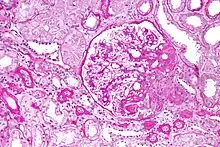

| Light micrograph of focal segmental glomerulosclerosis, hilar variant. Kidney biopsy. PAS stain. | |

On histology, FSGS manifests as scarring (sclerosis) to segments of glomeruli; moreover, only a portion of glomeruli are affected.[7][20][21] The focal and segmental nature of disease seen on histology help to distinguish FSGS from other types of glomerular sclerosis.[21]

Diagnosis of FSGS is made by renal biopsy that includes at least fifteen serial cuts with at least eight glomeruli.[31][32] Histologic features include sclerosis (scarring) of a portion (average: 15%) of the glomerular space, with only a portion of glomeruli manifesting any sclerosis.[32]